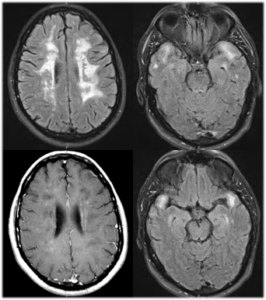

Idiopathic intracranial hypertension (IIH), sometimes called by the older names benign intracranial hypertension (BIH) or pseudotumorcerebri (PTC), is a neurological disorder that is characterized by increased intracranial pressure (pressure around the brain) in the absence of a tumor or other disease. The symptoms are headache, nausea, and vomiting, and sometimes pulsatiletinnitus (buzzing in the ears synchronous with the pulse), diplopia(double vision) and other visual symptoms. The increased pressure may lead to swelling of the optic disc in the eye. Swelling of the optic disc can progress to vision loss.

Older treatments of IIH included repeat lumbar punctures, medications that decrease production of CSF, surgical decompression of the optic nerve (optic nerve sheath fenestration), surgical shunting of the CSF from the spine to the abdomen (lumboperitoneal shunt), CSF shunting from the brain to the abdomen (ventriculoperitoneal shunt), and even CSF shunting from the brain to the heart (ventriculoatrial shunt).

New research demonstrates excellent clinical outcomes for the treatment of IIH by minimally invasive endovascular methods. These endovascular treatments involve placement of intracranial angioplasty balloons and stents across areas of narrowing (stenosis) within the cerebral venous circulation that remove blockages and relieve the elevated intracranial pressure.